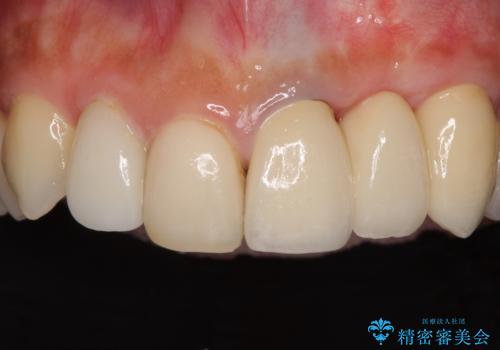

歯肉移植を用いた前歯のオールセラミックブリッジ

折れている前歯は抜歯をし、痩せてしまう歯肉は移植術により増大させることで審美面を回復した後、オールセラミックブリッジにて補綴することとしました。

インプラントかブリッジか悩むところでしたが、既に治療されている前歯のクラウン周りの変色が気になっていたため、ブリッジにより色調を合わせたオールセラミックを装着することを選択しました。

歯肉ラインや歯の形態、色調を整えることができ、患者様には大変満足していただきました。